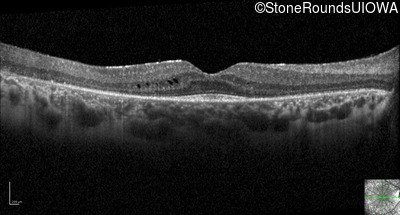

Visit at age: 21 years

Optical Coherence Tomography - Right - 20/25 -2

Exemplar / OCT Stack